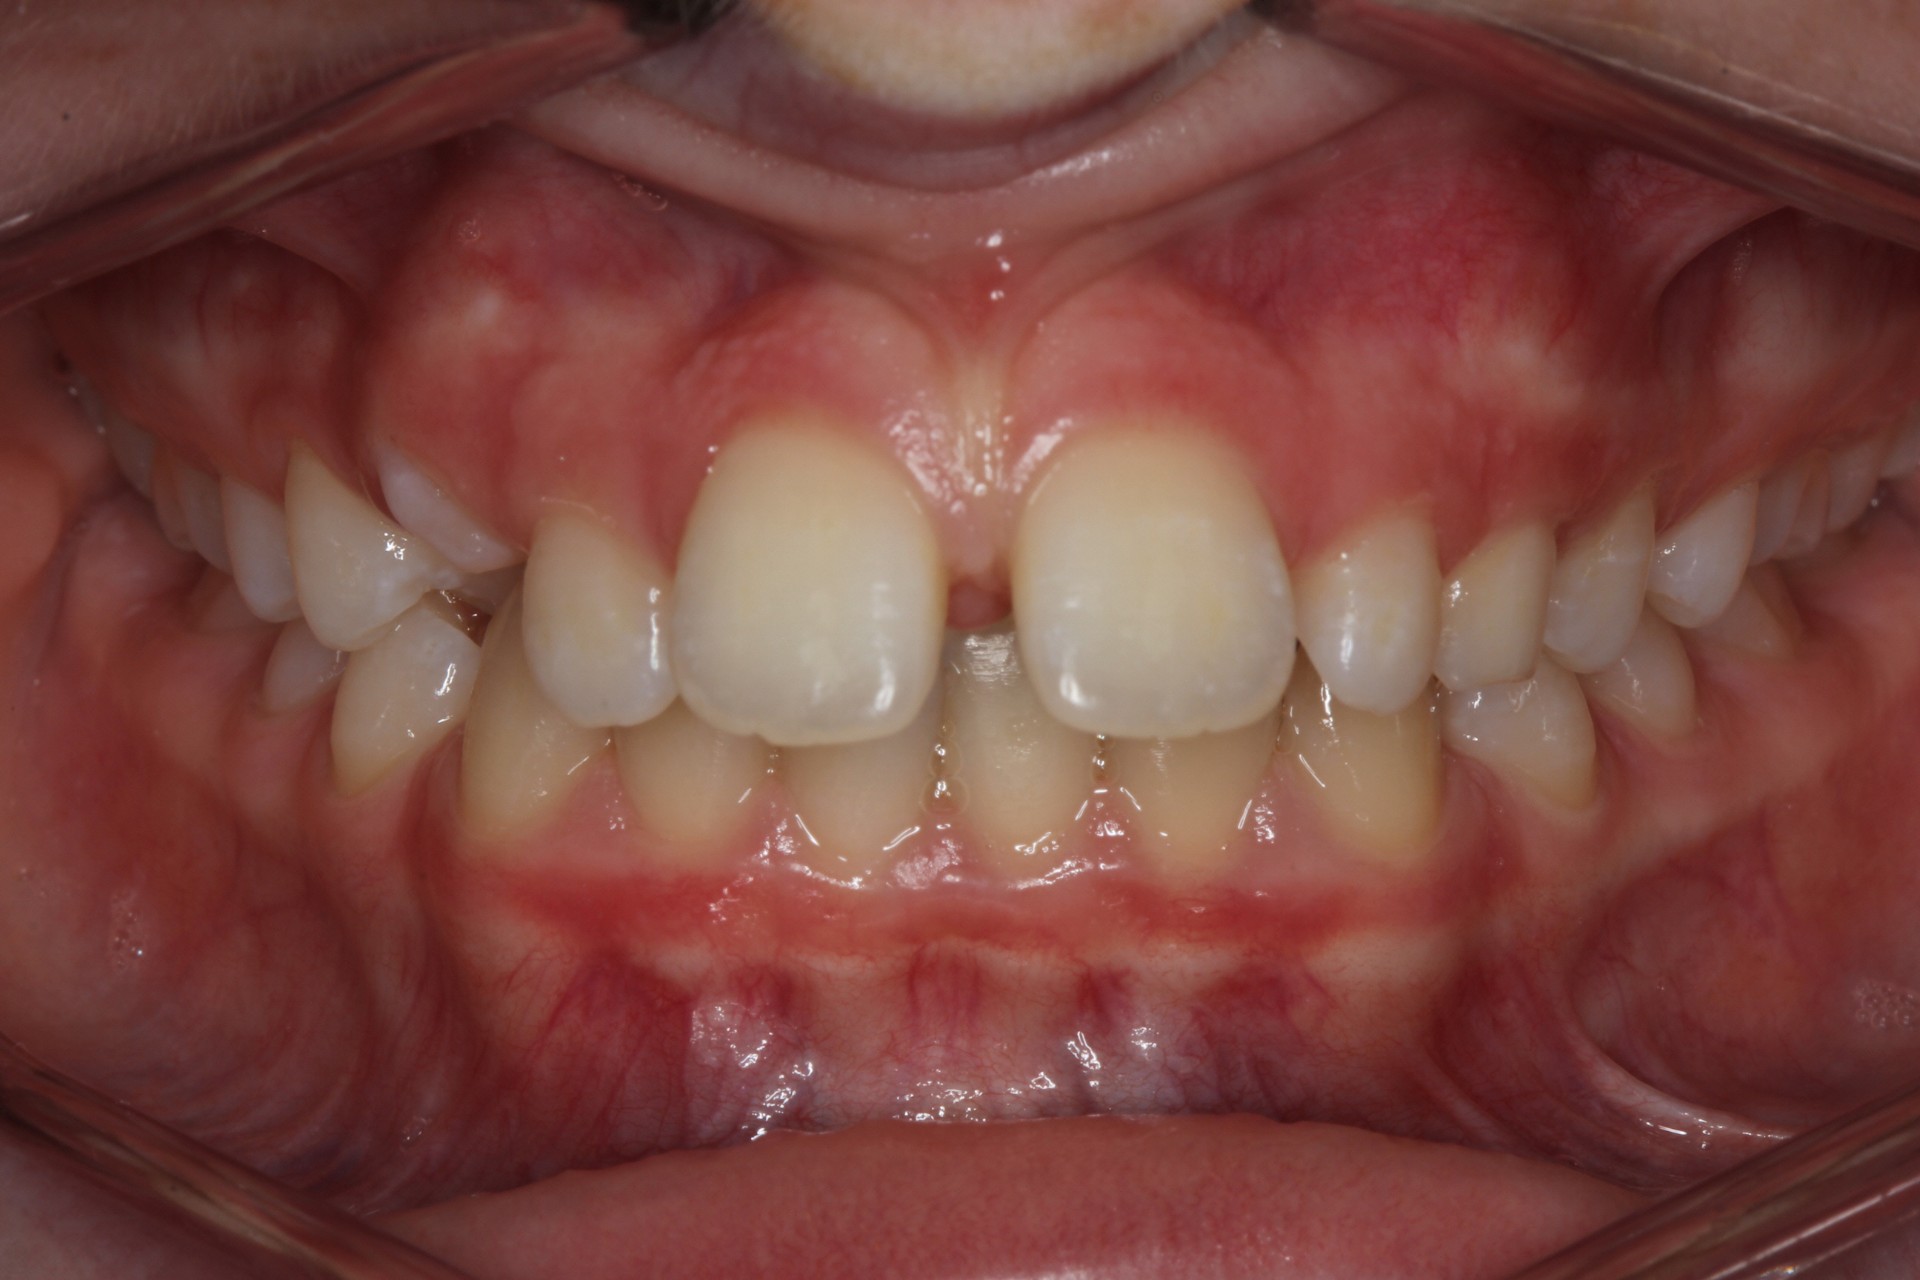

Protruding front teeth with midline diastema – Child case